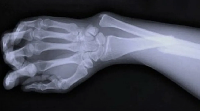

В случае перелома шейки бедра компания МосРентген Центр госпитализирует в Склиф для эндопротезирования.